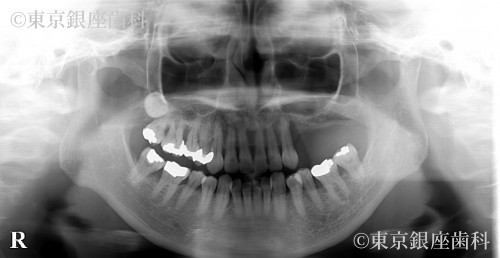

歯周病がひどく悪化し、動揺も激しくなった左上奥歯三本の歯を紹介元のクリニックの診断と同様、抜歯する必要がありました。歯科治療に対する恐怖心がとても強く、また抜歯の経験がなかったため、静脈内鎮静を併用しての治療を計画しました。歯を抜いた後、およそ5ヶ月の間に、骨が回復する期間を設け、その後歯科インプラント手術を予定しました。上顎左側、奥歯の骨の厚みが薄く、インプラントが固定される骨量が不足していたため、上顎洞内に骨を足す治療(以下サイナスリフトと呼ぶ)を併用し、三本のインプラントを埋入する計画を立てました。また抜歯後およびインプラント体と骨が結合するまで6か月の治癒期間中は、食事が不自由しないように、仮の義歯を作製し使用してもらう計画を立てました。

上顎左側の奥歯は、歯周病の進行が激しく、顎の骨の吸収がとても大きいことが認められました。上顎洞までの骨の量が不足していたため、サイナスリフトを併用したインプラント手術が必要でした。抜歯後およびインプラント体と骨が結合するのを待つ期間中に仮の入れ歯を装着してもらいましたが、患者様の術前当初のお話しにあったように違和感があり、インプラントでの口腔機能回復を選択してよかったとのお言葉を頂きました。また抜歯やインプラント手術などの外科治療時には。静脈内鎮静を併用して治療に臨めたので、歯科に対する恐怖心が和らいだとの事でした。現在、経過順調に定期健診を受診されておられます。